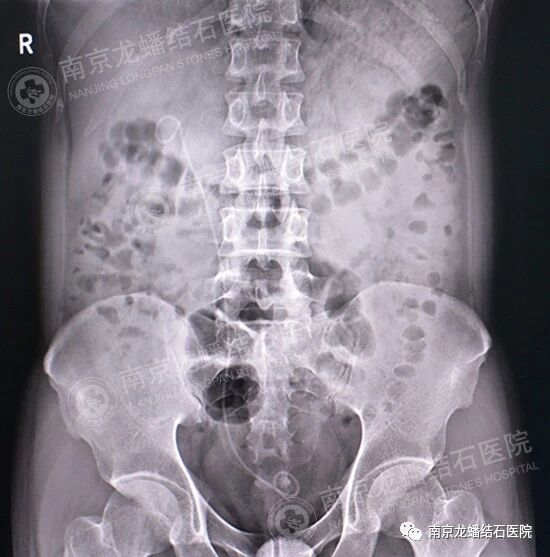

到院后,经过专业的全面系统检查,确诊为“右输尿管下段结石伴右肾积水”。针对韦先生的病情,医院泌尿结石团队讨论后决定,通过“经尿道右输尿管镜钬激光碎石取石术”为其治疗。

2019年5月17日上午15点30分,韦先生在全身麻醉的情况下进行手术。于韦先生的右输尿管上段见一枚结大小约0.6cm的淡黄色结石,予钬激光碎石,用取石网篮将其取出,反复探查输尿管上段,未见结石残留后束手术。